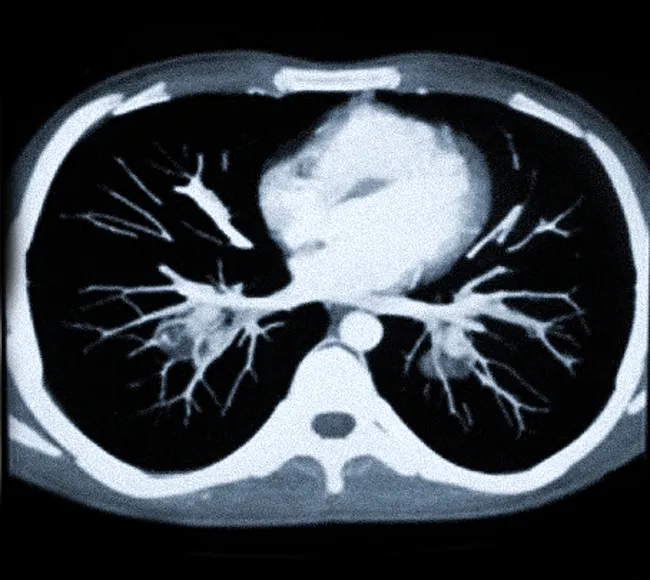

Что покажет КТ грудной аорты и легочной артерии

На изображениях, полученных в результате КТ грудной аорты и легочной артерии, можно увидеть анатомическое строение, конфигурацию, диаметр сосудов и структуру их стенок.

КТ грудной аорты и легочной артерии позволяет выявить:

- тромбы;

- опухолевые образования;

- пороки развития сосудов;

- атеросклеротические бляшки;

- травмы стенок сосудов.

Как осуществляется КТ-ангиография легочных артерий?

В ходе процедуры пациенту вводят контрастное вещество, что способствует лучшей визуализации органов. Сканирование займет около 15 минут, а результаты будут готовы в течение суток. КТ-ангиография легочных артерий позволяет выявить такие заболевания, как эмболия легочной артерии, стеноз и аневризмы сосудов. Процедура является безболезненной и безопасной, однако у некоторых пациентов могут возникнуть временные реакции на контрастное вещество, такие как неприятные ощущения в теле или легкое тепло.